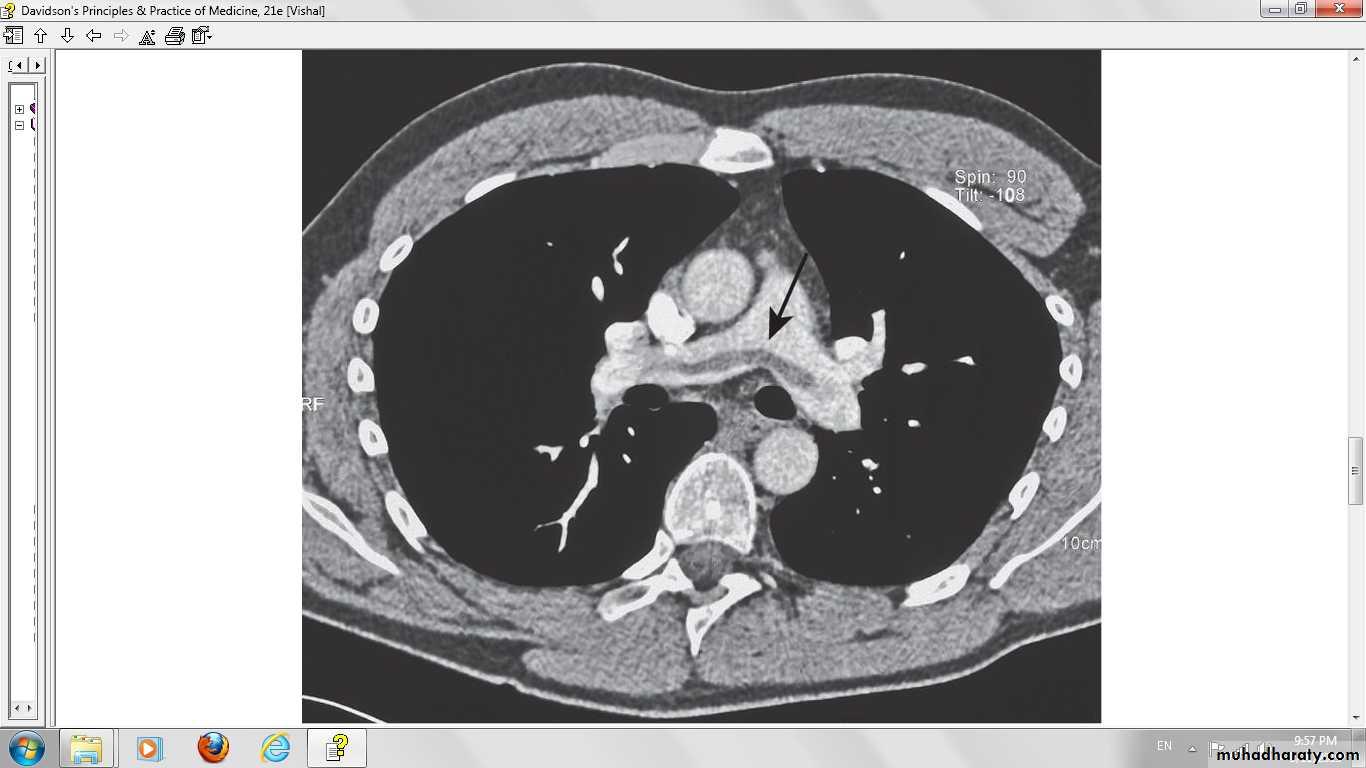

Spiral computed tomographic image of acute pulmonary emboli in both main pulmonary arteries in a postoperative patient with the sudden onset of dyspnea, hypoxemia, and hypotension.

CT

Helical CT pulmonary angiography sensitive and very specific.